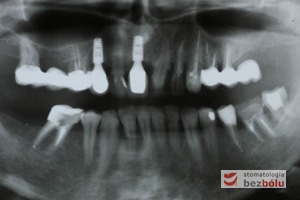

Pozabiegowa kontrola radiologiczna - ocena pozycji wprowadzonych wszczepów i kontrola po leczeniu endodontycznym

Pozabiegowa kontrola radiologiczna – ocena pozycji wprowadzonych wszczepów i kontrola po leczeniu endodontycznym